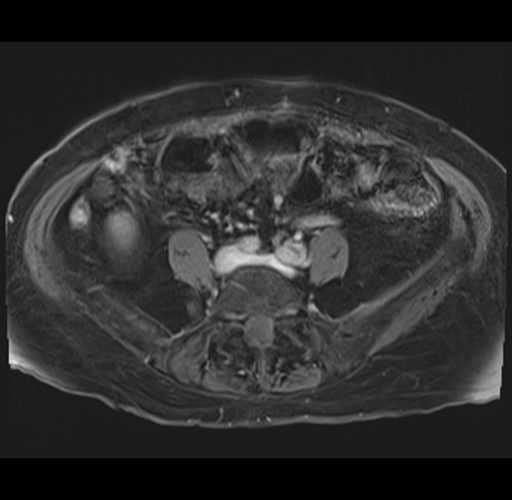

MRI T1

Imaging analysis

Based on your CT findings, which issue(s) would give reason for "planned slowing down moment(s)" in this case?

Considering a standard right hepatectomy procedure, what step(s) of the operation would you do differently in this case?